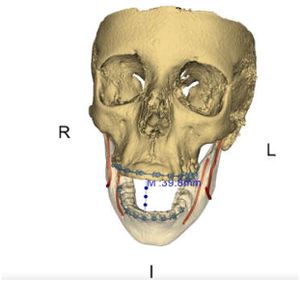

From 3D Imaging to 3D Printing in Dentistry - A Practical Guide

Publication: Int J Comput Dent. 2018;21(4):345-56. PMID: 30539177. Authors: Moser N, Santander P, Quast A. Institution: Department of Oral and Maxillofacial Surgery, University Medicine Göttingen, Göttingen, Germany. Abstract: 3D imaging in dentistry plays an essential part in diagnostics and treatment planning. To transform digital images into a real object that can be experienced haptically may provide new opportunities to practitioners regarding patient communication, skills training, and treatment planning. Therefore, the aim of this article is to provide a practical guide from 3D imaging to 3D printing using low-cost printers and open source software; the authors used 3D Slicer software and a Meshmixer printer, including the printer's own software. The article presents step-by-step instructions on how to perform rapid prototyping via fused deposition modeling (FDM) and stereolithography (SLA). As an example, we printed the skull of a patient with Saethre-Chotzen syndrome who was undergoing maxillofacial surgery. The protocol explained here should enable the technically interested clinician to produce patient-specific 3D models in-house, prefabricate osteosynthesis plates, and take advantage of the benefits of 3D printing for dentist-patient communication. |